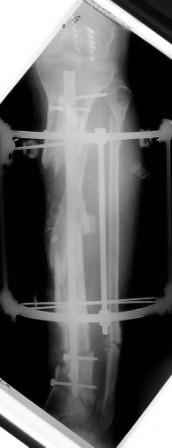

1) Наложить Аппарат Илизарова. В аппарате восстановить оси трех смещенных относительно друг-друга фрагментов большеберцовой кости. Устранить вальгусную деформацию дистального отдела большеберцовой кости.

Что и было выполнено.

- Была выполнена репозиция в аппарате (рис1)